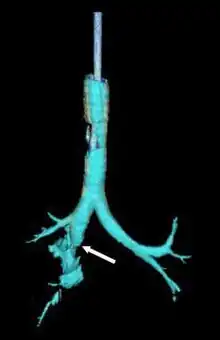

| Reconstruction of the trachea and bronchi with x-ray computed tomography showing disruption of the right main bronchus with abnormal lucency (arrow)[1] | |

- 1 2 3 Le Guen M, Beigelman C, Bouhemad B, Wenjïe Y, Marmion F, Rouby JJ (2007). "Chest computed tomography with multiplanar reformatted images for diagnosing traumatic bronchial rupture: a case report". Critical Care. 11 (5): R94. doi:10.1186/cc6109. PMC 2556736. PMID 17767714.